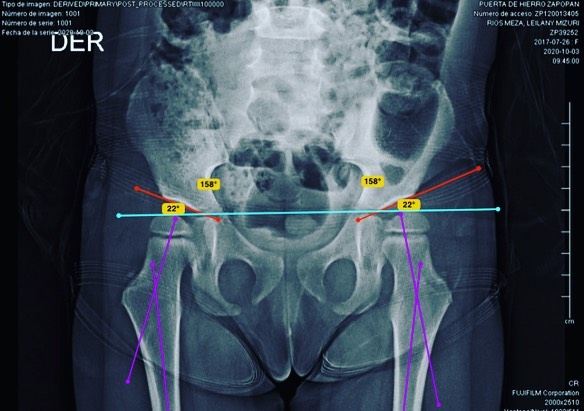

Displasia de cadera

Quiero compartirles que doy de alta a mi pacientita Leilany, de 5 años. La operé por displasia de cadera causada por coxas valgas (región proximal del fémur muy vertical), que alteraba la morfología de su cadera y provocaba disfunción a largo plazo. Le realicé un tratamiento quirúrgico para corregir la deformidad y ahora está al 💯, lista para jugar y hacer travesuras. 🎉